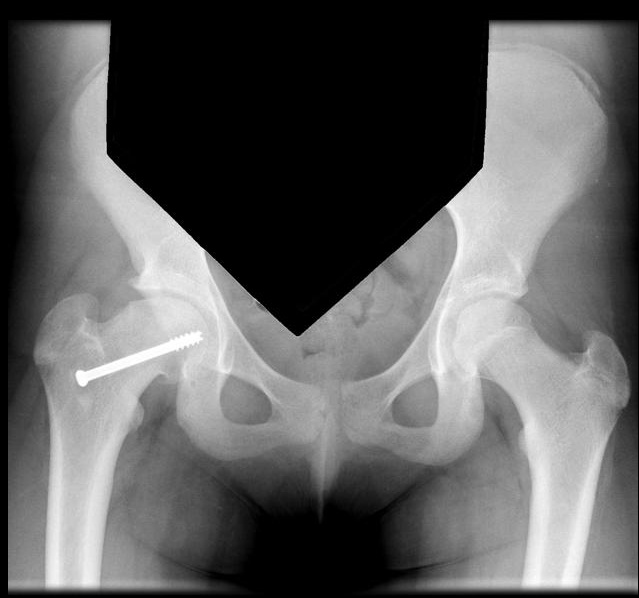

X-ray imaging including AP and frog leg lateral of both hips shows the epiphysis remaining within the acetabulum while the neck displaces anteriorly and externally rotates leaving the head posterior to the neck. An early radiographic finding is epiphysiolysis where the growth plate is widened or shows increased lucency.,

Treatment

Treatment options are primarily surgical with percutaneous pinning of the slipped side. Treatment of this condition is emergent.,